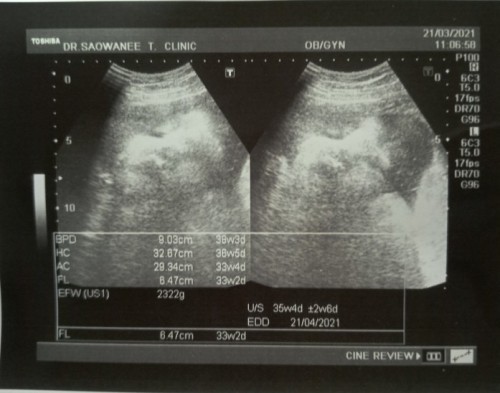

37 สัปดาห์ ลูกน้ำหนักน้อยจัง

มีใครซาวด์แล้วน้ำหนักลูกน้อย แต่คลอดออกมาน้ำหนักเกินที่ซาวด์บ้างคะ